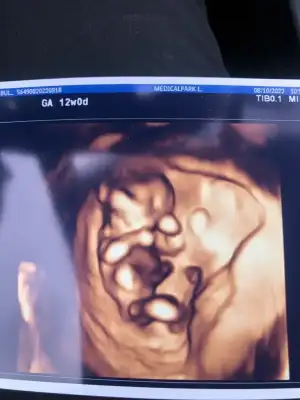

doktor da 11+3 te ki kontrolüne göre bişey söylemek için erken ama kızımsı duruyor demişti

doktor da 11+3 te ki kontrolüne göre bişey söylemek için erken ama kızımsı duruyor demişti değerler de normal gözüküyor sanırım.

ben de cok tatlı bi kız gübi hissertm sağlıkla al kucagına inşallah